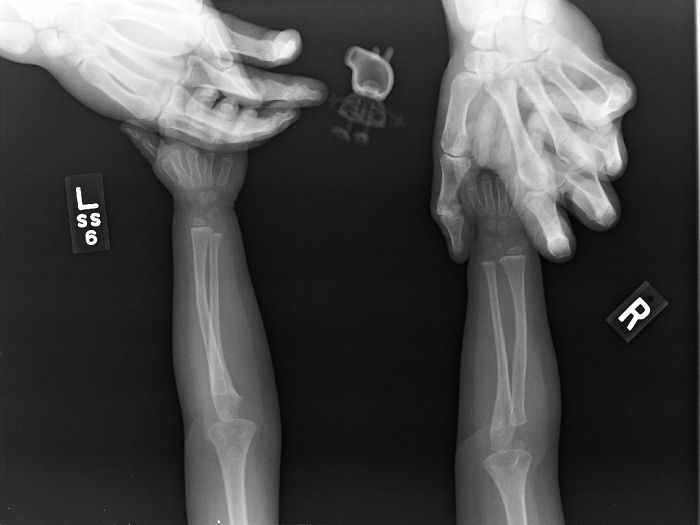

My (Nearly 60-Years-Old) Father's Arm After Being Thwomped By A Cow This Morning